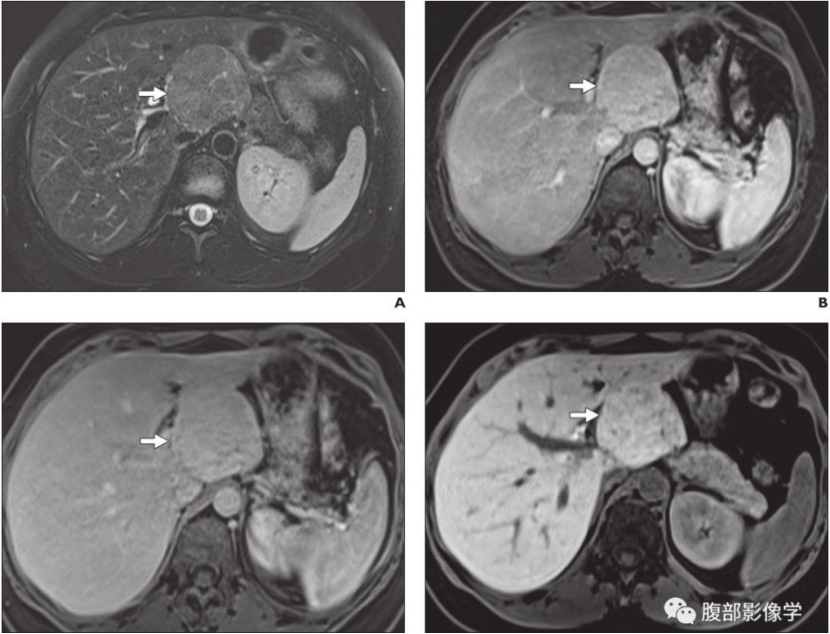

由于出血或脂肪变性,CT呈稍高或低密度,T1WI呈高或低信号,T2WI呈不均匀高信号,动态增强呈不均质强化(与发生脂肪变 、糖元沉积 、钙化及出血、坏死相关);中央瘢痕不显示或不强化。

女性29岁,长期口服避孕药,T2WI等信号+肝胆期高摄取+包膜,不典型FNH。